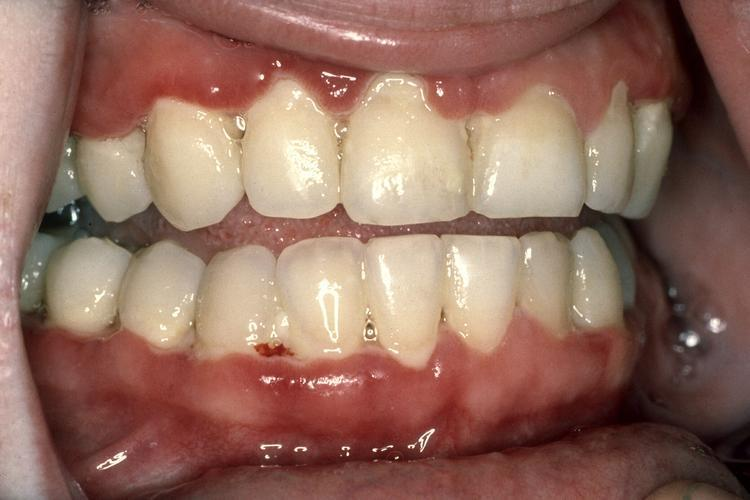

慢性牙周炎:牙面常有大量牙石,牙龈呈现不同程度的慢性炎症,颜色呈鲜红或暗红色,质地松软,点彩消失,牙龈水肿。探诊出血甚至溢脓。早期已有牙周袋和牙槽骨吸收,程度较轻,牙尚不松动。晚期深牙周袋形成后,牙松动,咀嚼无力或疼痛,甚至发生急性牙周脓肿。

慢性牙龈炎:部分慢性牙龈炎者可见龈缘糜烂或有肉芽增生,牙龈组织水肿、松软、脆弱,同时龈沟探查深度>3mm,可出现出血现象,且龈沟液量增多。